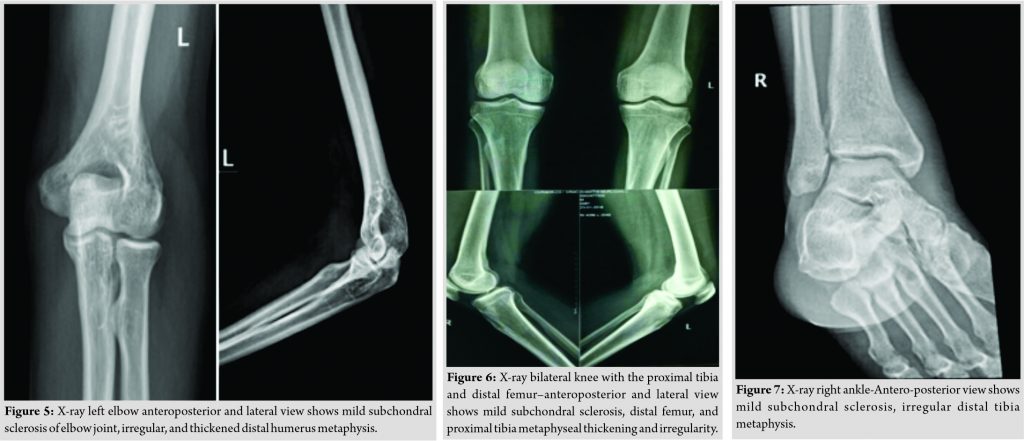

Systemic examination was notable for mild hepatosplenomegaly, and musculoskeletal examination revealed swelling and tenderness over left elbow, bilateral knee, and right ankle with the restricted left elbow, bilateral knee, and ankle joint mobility. Initial evaluation revealed a normal white cell count (8400 cells/mm3, neutrophils 60%) and elevated inflammatory markers (erythrocyte sedimentation [ESR] rate 113 mm/h, C-reactive protein (CRP) 72 mg/L).X-ray of left elbow revealed distal humerus metaphyseal cortical irregularity and thickening with subchondralsclerosis (Fig. 5).

The patient initially underwent left elbow arthrotomy and surgical debridement. Per-operative pus was evacuated from intracapsular and intramuscular region. Intra-operative pus culture was sent. Post-operative pus culture from left elbow shows Staphylococcus aureus growth and treated with intravenous cefoperazone-sulbactam antibiotic for next 2 weeks. The patient improved briefly, after 2 weeks of intravenous antibiotic patient presented again with recurrence of same symptoms. Blood culture and echo (trans-esophageal echocardiography,trans-thoracic echocardiography)weredone to rule out infective endocarditis. X-rayof bilateral knee shows proximal tibia and distal femur metaphysis cortical irregularity and thickening (Fig. 6).

X-ray right ankle (Fig. 7) shows decrease joint space with mild subchondral sclerosis. Technetium 99-MDP whole-body scintigraphy shows increase uptake in left elbow, bilateral knee and right ankle (Fig. 8). In view of occupation, uncontrolled diabetes mellitus and non-improvement, melioidosis was suspected following which patient underwent bilateral knee and right ankle arthrotomy and surgical debridement. Per-operatively, he was noted to have involvement of bilateral knee and right ankle and intracapsular and intramuscular pus collection. Tissue sample for PCR for melioidosis was positive, and serial blood cultures grew Gram-negative bacilli, later identified asB.pseudomallei. Gram staining revealed typical bipolar stained B. pseudomallei (Fig. 9).